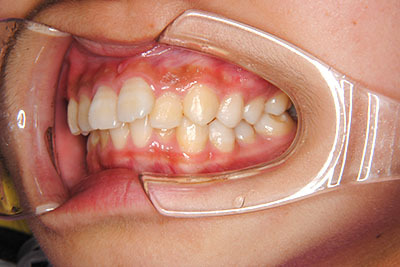

歯が乳歯から永久歯に生え変わった小学生高学年や、中高生でも矯正治療に手遅れということは全くありません。

成長中の顎の骨を矯正できたり、この時期の矯正はおとなになってから矯正治療を始めるよりも短期間で済むことがほとんどです。当院だとおおよそ1年で動的治療(マルチブラケット装置をつける期間)が終わることが多いです。